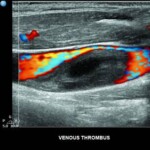

Μολονότι σήμερα ὅλο καὶ πιὸ συχνὰ καθόμαστε, ἐνίοτε τὰ βράδυα αἰσθανόμαστε τὰ πόδια μας βαρειὰ ἢ βλέπουμε τὰ σφυρά μας ἐλαφρῶς πρησμένα. Λοιπὸν τότε πιθανὸν νὰ βρισκόμαστε στὴν ἀρχὴ μιᾶς φλεβικῆς ἀνεπάρκειας. Ἐπειδὴ ὁπωσδήποτε θεωροῦμε τὴν ποιότητα τῆς ζωῆς μας καὶ τὴν ὀμορφιὰ βασικὸ στοιχεῖο τῆς καλῆς ψυχολογίας, μπορεῖ προσωρινὰ νὰ βρίσκουμε καταφύγιο σὲ ἐμβαλωματικὲς λύσεις (παντελόνι), ὅμως ἀργὰ ἢ γρήγορα θὰ καταλήξουμε στὴν λεγόμενη φλεβικὴ ἀνεπάρκεια μὲ κύρια ἐκδήλωση τοὺς κιρσούς (Veneninsuffizienz -Varikosis). Τότε τὸ θέμα περιέρχεται κατ’ ἀρχὴν στὴν ἀρμοδιότητα τοῦ ἀκτινολόγου, ὁ ὁποῖος θὰ διενεργήσει τὴν ἐξέταση Triplex φλεβῶν κάτω ἄκρων καὶ ἀφοῦ ἐκεῖνος θέσει τὴν διάγνωση, ἐν συνεχεία παίρνει σειρὰ ὁ ἀγγειοχειρουργός, ποὺ θὰ δώσει καὶ τὴν τελικὴ λύση!!